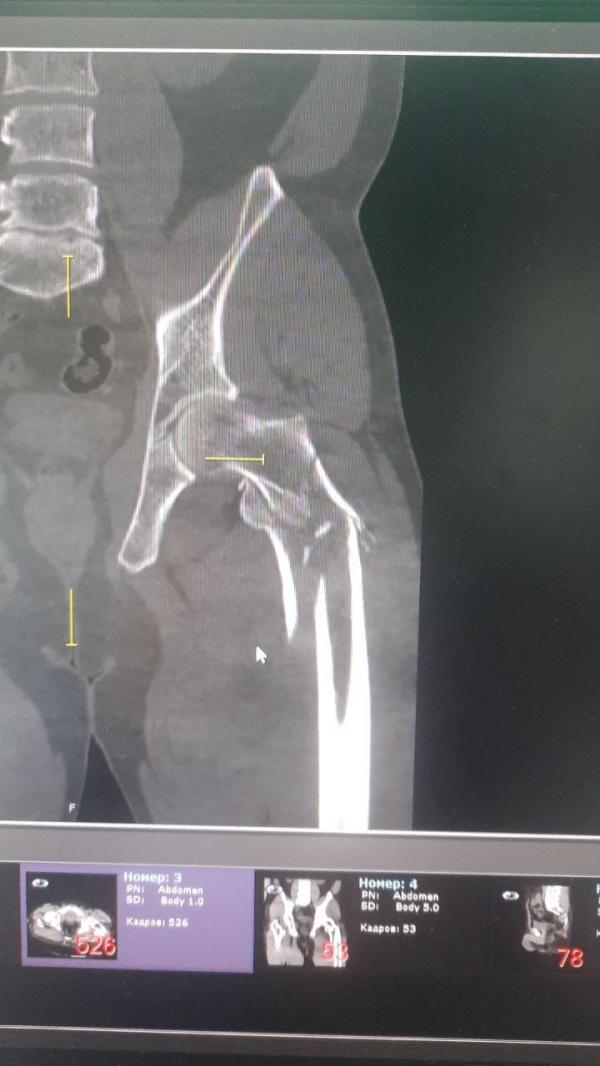

Как рассказали в минздраве региона, мотоциклист Алексей попал в ДТП, в результате которого получил серьезные травмы: тяжёлую сочетанную травму рёбер с обеих сторон, ушиб лёгкого, вывих предплечья справа с переломом локтевого отростка, переломом лучевой кости, вывихом локтевой кости в лучезапястном суставе, а также многооскольчатые переломы бёдер и голени. Также мужчина потерял много крови. Бригадой «скорой» его оставили в больницу Березовского.

Лечащий врач пациента, травматолог-ортопед Павел Гулаков и его коллеги одну за другой выполнили три операции: сначала стабилизировали правую ногу, которая наиболее сильно пострадала при ДТП, затем прооперировали левую ногу и правую руку. Все вмешательства прошли успешно.